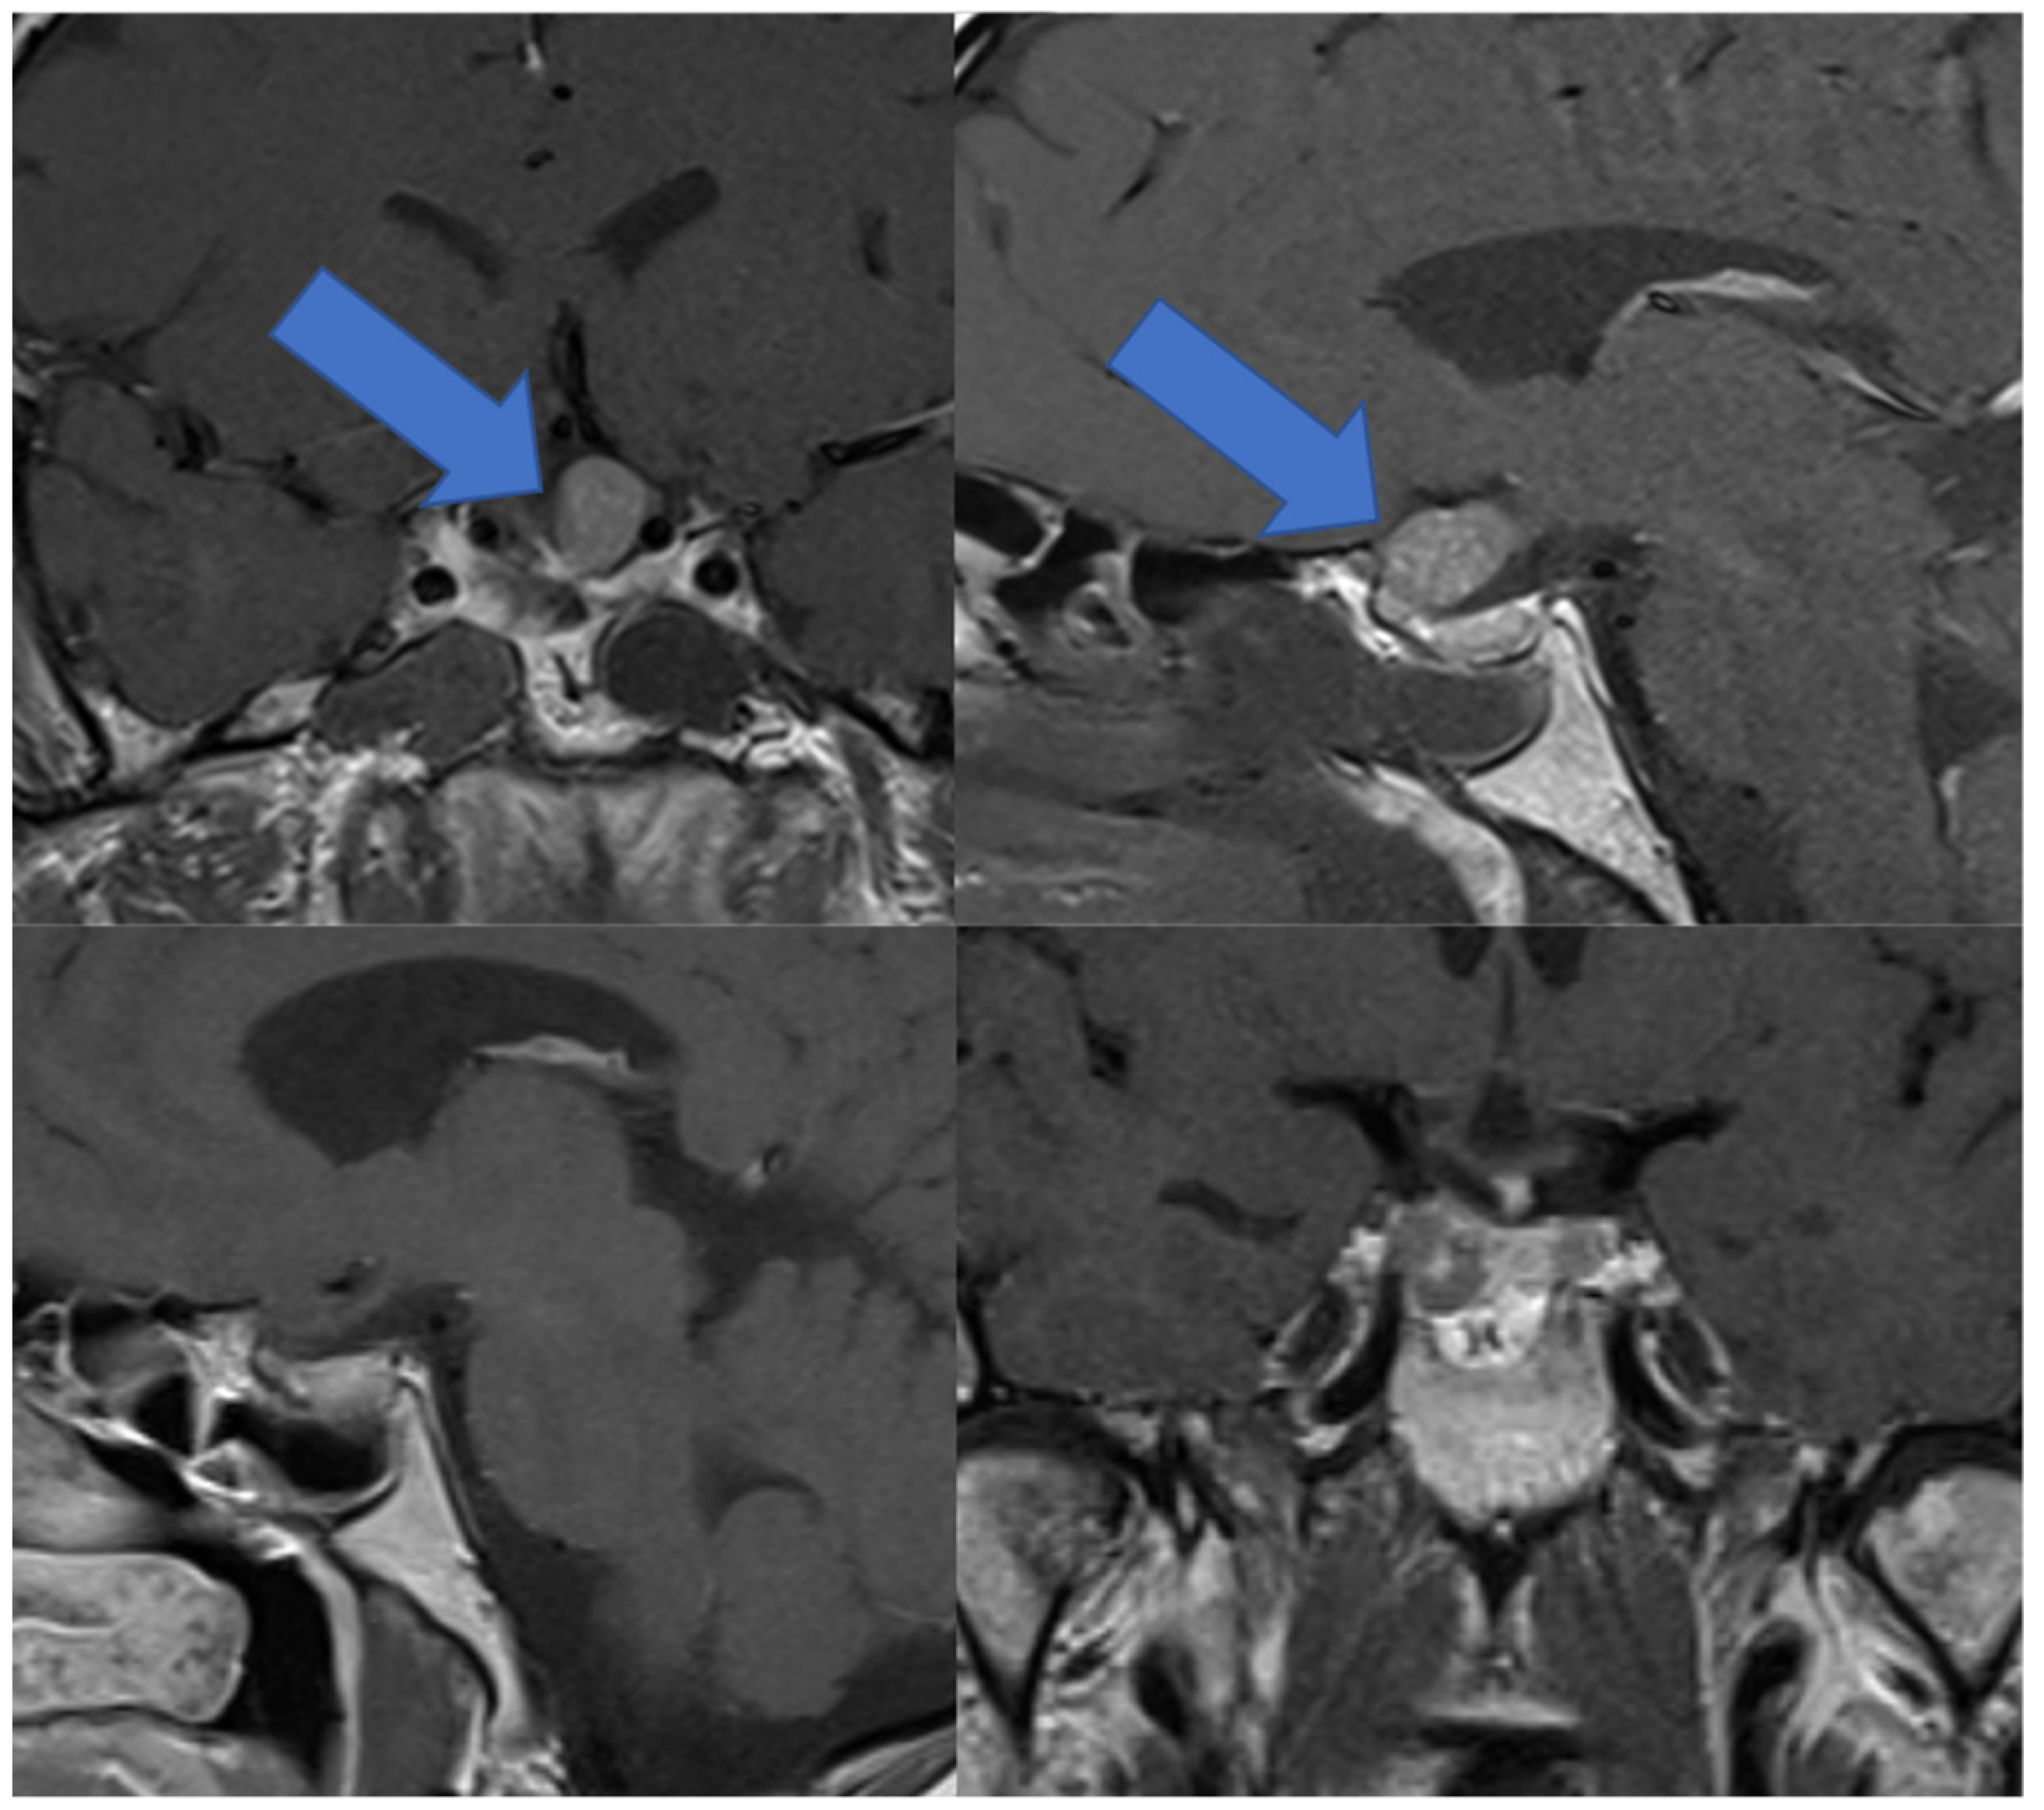

3.6. Illustrative Case